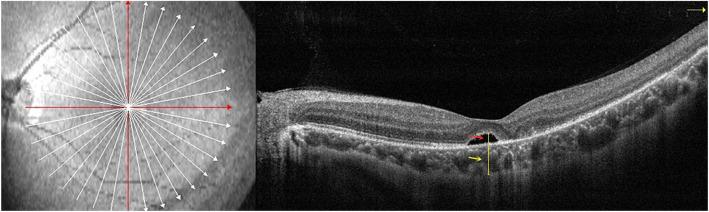

The purpose of this study is to assess the absorption of subretinal fluid (SRF) after scleral buckling (SB) surgery for the treatment of rhegmatogenous retinal detachment (RRD). We also examined related factors that may affect the delayed absorption of SRF.

METHODS

This retrospective study included patients who underwent successful SB surgery for the treatment of macula-off RRD and in which the retina was reattached after the surgery. The patients were categorized according to gender, duration, age, the number, and location of retinal breaks. Subfoveal choroidal thickness (SFCT), height of subretinal fluid (SRFH), and the choriocapillaris flow density (CCFD) within 3 × 3 mm macular fovea were included. Delayed absorption was determined by the SRF that remained unabsorbed for 3 months after the procedure. The endpoint was determined when the SRF could no longer be observed.

RESULTS

A total of 62 patients (63 eyes) were enrolled. In 35 eyes (56.45%) SRF was completely absorbed and in 28 (43.55%) eyes delayed absorption of SRF in macular areas was observed at 3 months after surgery. A young age (< 35 years), inferior retinal breaks were associated with good outcomes by applying multivariable analysis on the rate of SRF absorption after SB instead of gender, the number of breaks, and duration (p < 0.05). CCFD was significantly different between the SRF group and the non-SRF group after SB (0.66 ± 0.04% vs 0.63 ± 0.05%, P < 0.05). SRFH showed a moderate positive correlation with SFCT (r = 0.462, p = 0.000), however, using binary logistic regression analysis it was determined that SFCT was not related to the absorption of the SRF.

CONCLUSIONS

The absorption of SRF after SB may be correlated with choriocapillaris flow density. Age and location of breaks are significant factors affecting the absorption of SRF. The duration of disease is an uncertain factor due to several subjective reasons.